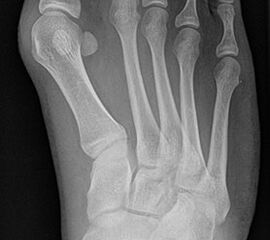

Bei einem juvenilen Hallux valgus handelt es sich um eine schon im Kindes – oder Adoleszentenalter 1 bestehende Valgusdeviation der großen Zehe bei Spreizfuß mit vergrößertem Intermetatarsalwinkel I / II aufgrund einer Adductionsstelllung des Metatarsale I – Metatarsaus primus varus.

Im Gegensatz zum Hallux valgus des Erwachsenen ist die Valgusabweichung der großen Zehe meist geringer ausgeprägt als bei Erwachsenen, der Intermetatarsalwinkel oft stark vergrößert. Die Angaben ab wann der Intermetatarsalwinkel als vergrößert gilt schwanken zwischen > 9° 2 und >14°3. Das Ausmaß der Beschwerden korrelieren nicht mit dem Auftreten und dem Schweregrad der Deformität (Zollinger 1990, Zollinger 1993). Begünstigend wirkt eine Schrägstellung des ersten Tarsometatasalgelenkes (Hefti 1998) und eine Hypermobilität dieses Gelenkes 2 in Kombination mit einer Bindegewebsschwäche. Häufig liegt eine positive Familienanamnese vor. In einer Untersuchung von Coughlin fand sich eine Vererbung über die mütterliche Linie in 72%, ein milder bis stark ausgeprägter Knick-Senkfuß in 17% (das entspricht der Quote von Knick-Senkfüßen in der Normalbevöl­kerung) aber in 22% ein Pes adductus, das ist wesentlich mehr als in der Normalbevölkerung zu erwarten wäre 4. Auch für Hefti (1998) gilt der Pes adductus als Komponente des Sichelfußes als begünstigend. Zur Inzidenz des Hallux valgus juvenilis finden sich je nach Autor verschiedene Angaben. Nach Auswertung von Schuluntersuchungen liegt die Häufigkeit zwischen 1,6 % bis 17% 56. Häufig tritt die Fehlstellung doppelseitig auf. Der Anteil der betroffenen Mädchen liegt 4-5x höher als bei Jungen (Lamprecht 2015).

Röntgen

Standard ist die belastete Röntgenaufnahme des Fußes dorso-plantar und seitlich. Günstig ist eine Röhrenkippung von 10°-20°, um die Gelenke der Lisfranc-Linie einsehen zu können.

• Hallux valgus Winkel

• Hallux valgus interphalangeus Winkel

• Intermetatarsalwinkel I zu II

• Distaler Metatarsale Gelenkwinkel (PASA)

• Form des Mittelfußknochenkopfes

• Winkel Metatarsale I Basis zum Os cuneiforme mediale

• Metatarsalindex

• Elevation/ Plantarisierung I. Strahl

• Pes metatarsus adductus

• Wachstumsfugen